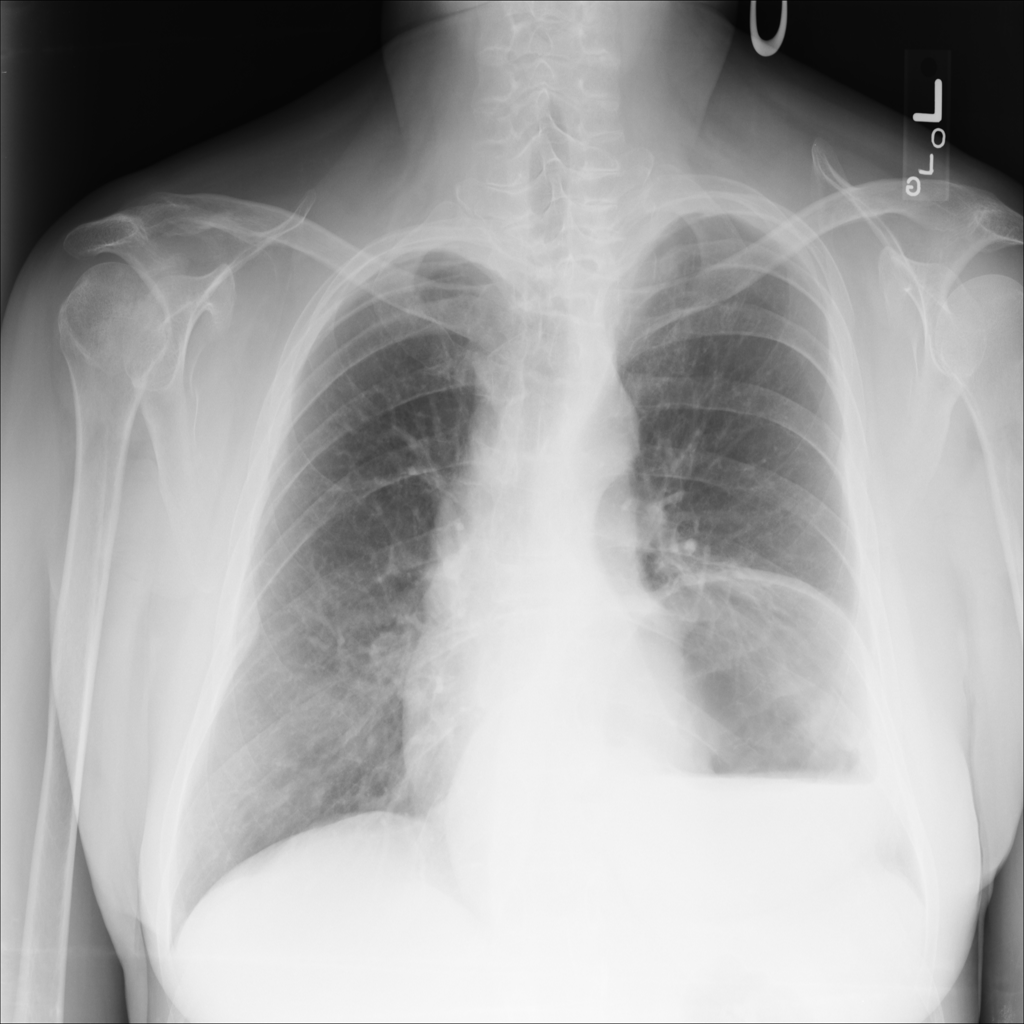

PAT-4F7E · IMG-000Hernia

PAT-4F7E · IMG-000

PA